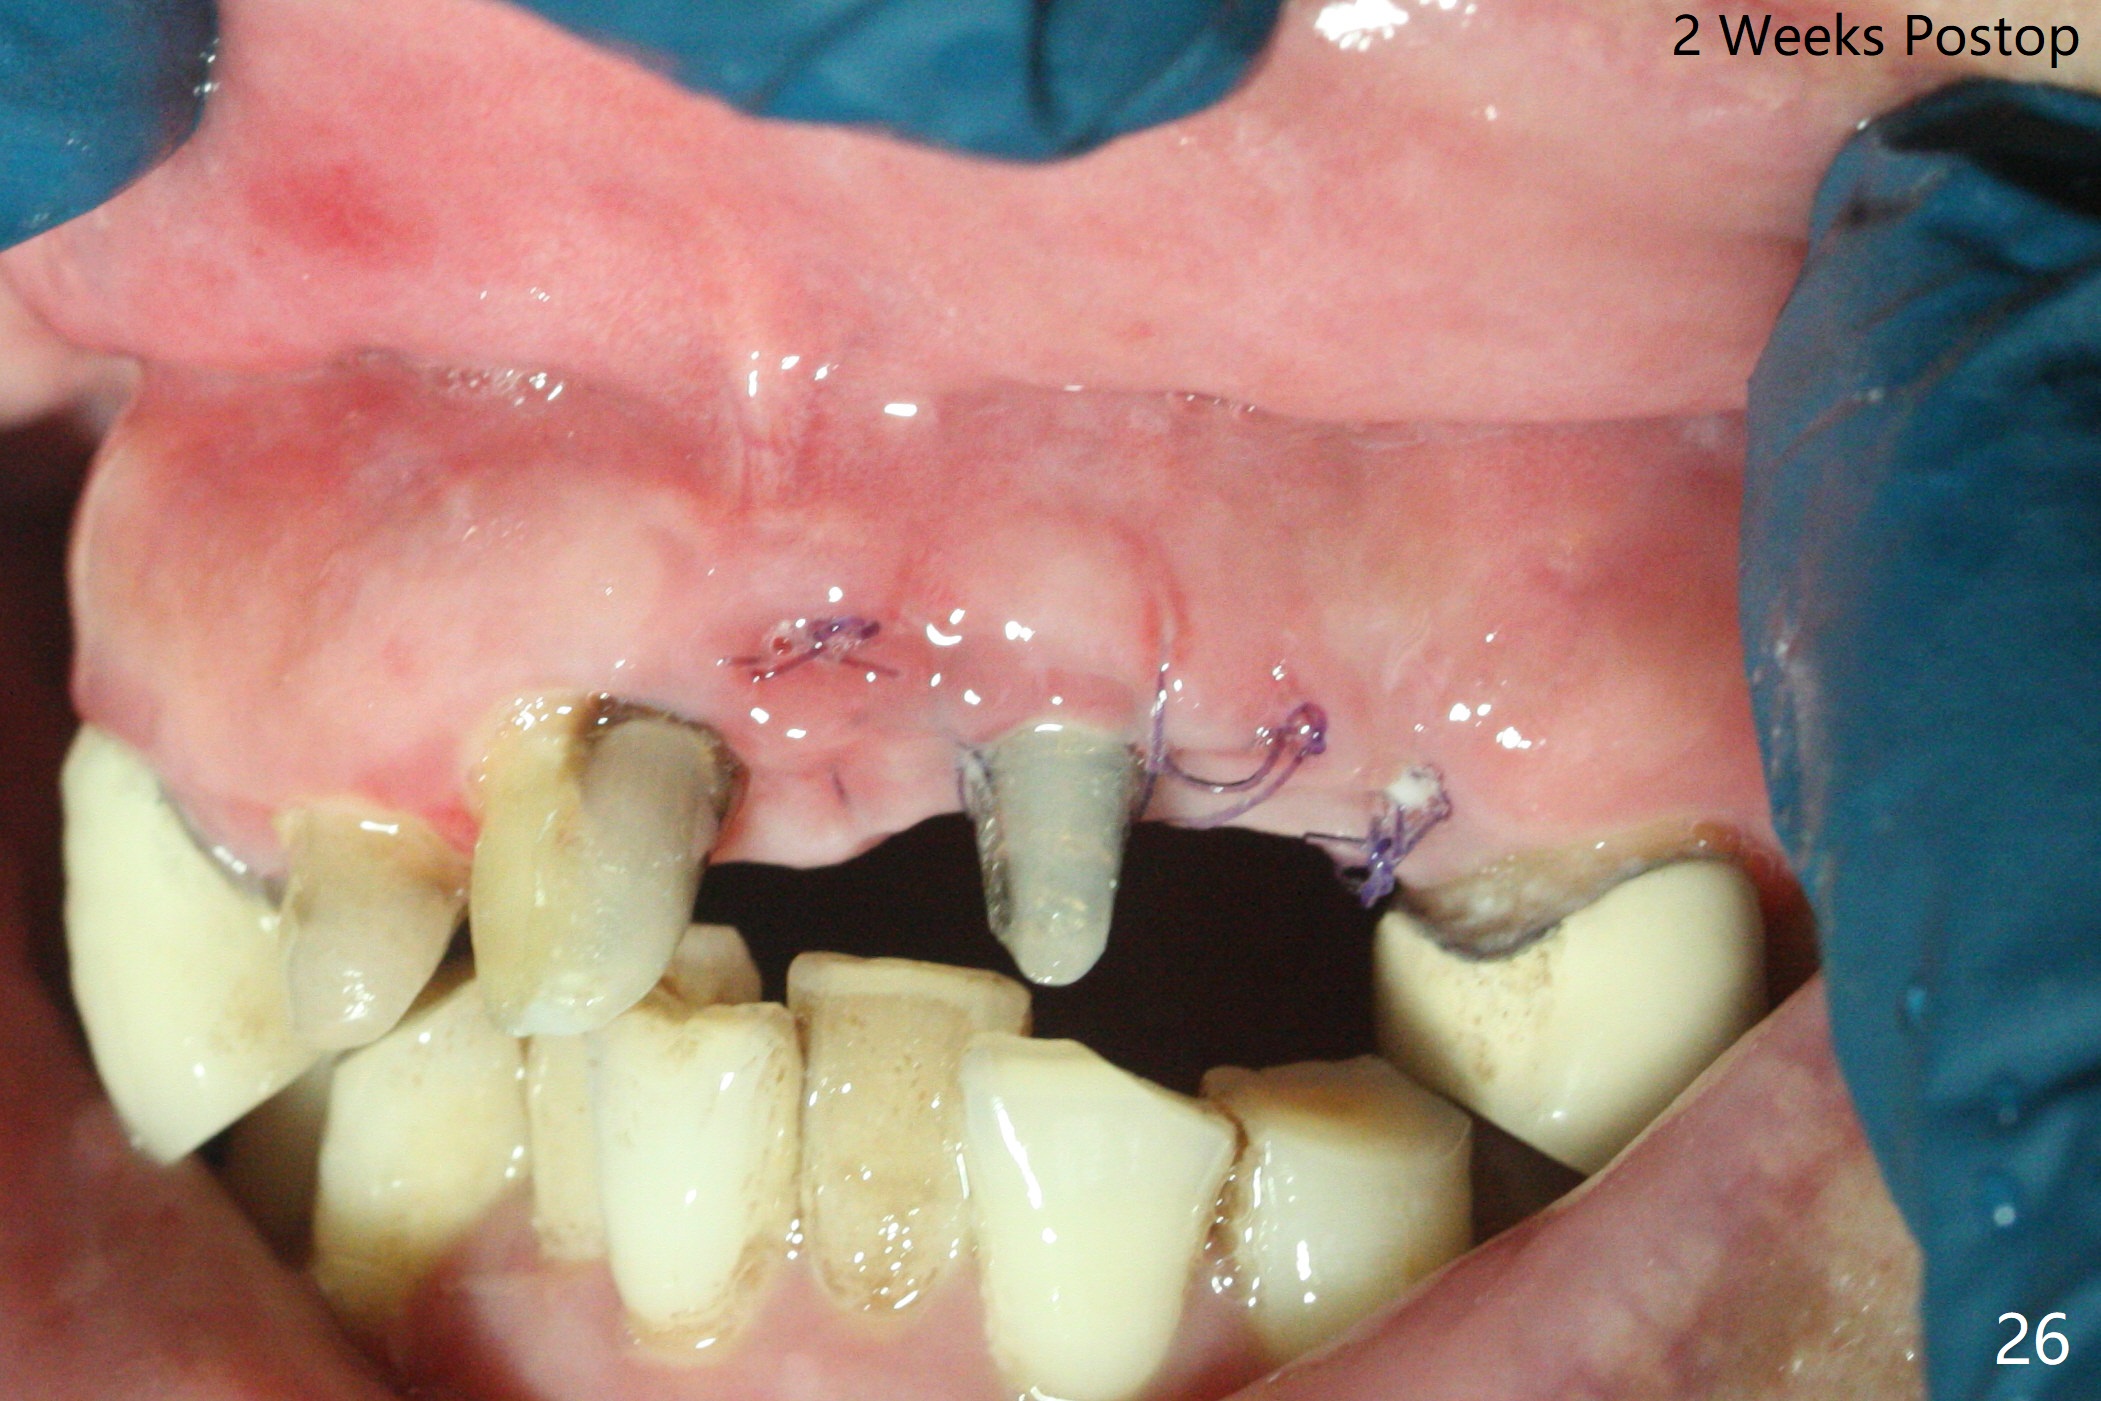

The mesiobuccal margin at #8 is redefined 4 weeks postop (Fig.14) so that the cervical end of the temporary crown is able to move mesially (Fig.13). The most coronal portion of the bone graft at #11 begins to be detached (*). The mesial portion of the abutment at #10 will be removed (curved white line) in the following week. After removing the most coronal portion of detaching bone graft at #11, acrylic is added to form a concave pontic (Fig.15 ^). With removal of the mesial portion of the abutment at #10, the retainer is moved distal (>). Pontics form at UL1 and 3 two months postop (Fig.16 *), while there is buccal atrophy at UL1,2 (Fig.17). 术后3个月植牙区牙龈形态良好(图十八),即将暴露,放置愈合基台。图十九是在右上1根管治疗时(基台放置后五天)拍摄。左上3术后3个月3个星期,1,2唇侧塌陷(图二十)。叶状植体处牙槽嵴往根尖萎缩(图二十一:^)。尽管做了松弛切口,放入事先预备的粘性骨粉后,几乎没有空间放置结缔组织移植物,恰好还没有取。放置PRF膜后,使用4-0 Monoglyc缝线缝合。牙龈似乎冠方移位(图二十二:箭头)。植骨后,唇侧仿佛饱满多了(图二十三:*)。骨粉放置于左上1,2唇侧和牙槽嵴(图二十四:*,与之前(图十九)对比)。后者有助于牙龈冠方移位,而前者有助于增加唇侧饱满度。植骨术后两周唇侧仍饱满(图二十五,六)。植骨后四个月牙冠粘固,两个月后,病人抱怨10号牙左右食物坎塞(图二十七),9/10牙冠撤除,10基台边缘加深,重做临时牙冠,同时增加9凹陷(pontic)。一个月后,9/10临时牙冠修整两次,11永久性牙冠撤除,也制备临时牙冠,外形明显改善(图二十八)。